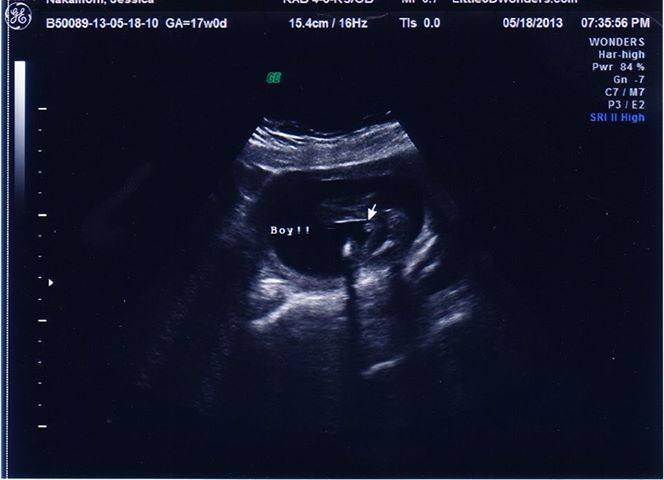

i went to another place to recheck gender... is this shot any better??Attachment 11321

I commented on in-gender but yes, much better :) This one shows boy parts.

I didn't see the original pic...but this one looks very boy :) Congrats!